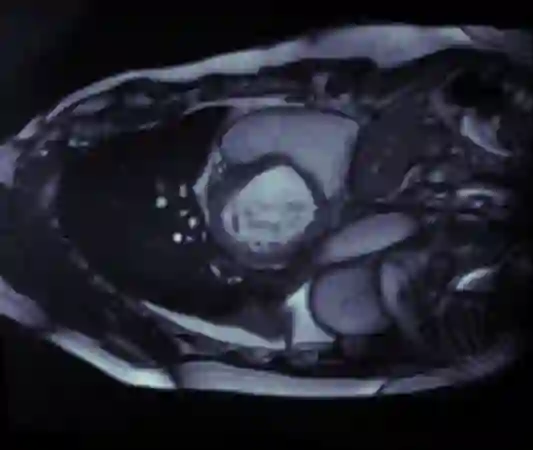

Supervised machine learning provides state-of-the-art solutions to a wide range of computer vision problems. However, the need for copious labelled training data limits the capabilities of these algorithms in scenarios where such input is scarce or expensive. Self-supervised learning offers a way to lower the need for manually annotated data by pretraining models for a specific domain on unlabelled data. In this approach, labelled data are solely required to fine-tune models for downstream tasks. Medical image segmentation is a field where labelling data requires expert knowledge and collecting large labelled datasets is challenging; therefore, self-supervised learning algorithms promise substantial improvements in this field. Despite this, self-supervised learning algorithms are used rarely to pretrain medical image segmentation networks. In this paper, we elaborate and analyse the effectiveness of supervised and self-supervised pretraining approaches on downstream medical image segmentation, focusing on convergence and data efficiency. We find that self-supervised pretraining on natural images and target-domain-specific images leads to the fastest and most stable downstream convergence. In our experiments on the ACDC cardiac segmentation dataset, this pretraining approach achieves 4-5 times faster fine-tuning convergence compared to an ImageNet pretrained model. We also show that this approach requires less than five epochs of pretraining on domain-specific data to achieve such improvement in the downstream convergence time. Finally, we find that, in low-data scenarios, supervised ImageNet pretraining achieves the best accuracy, requiring less than 100 annotated samples to realise close to minimal error.